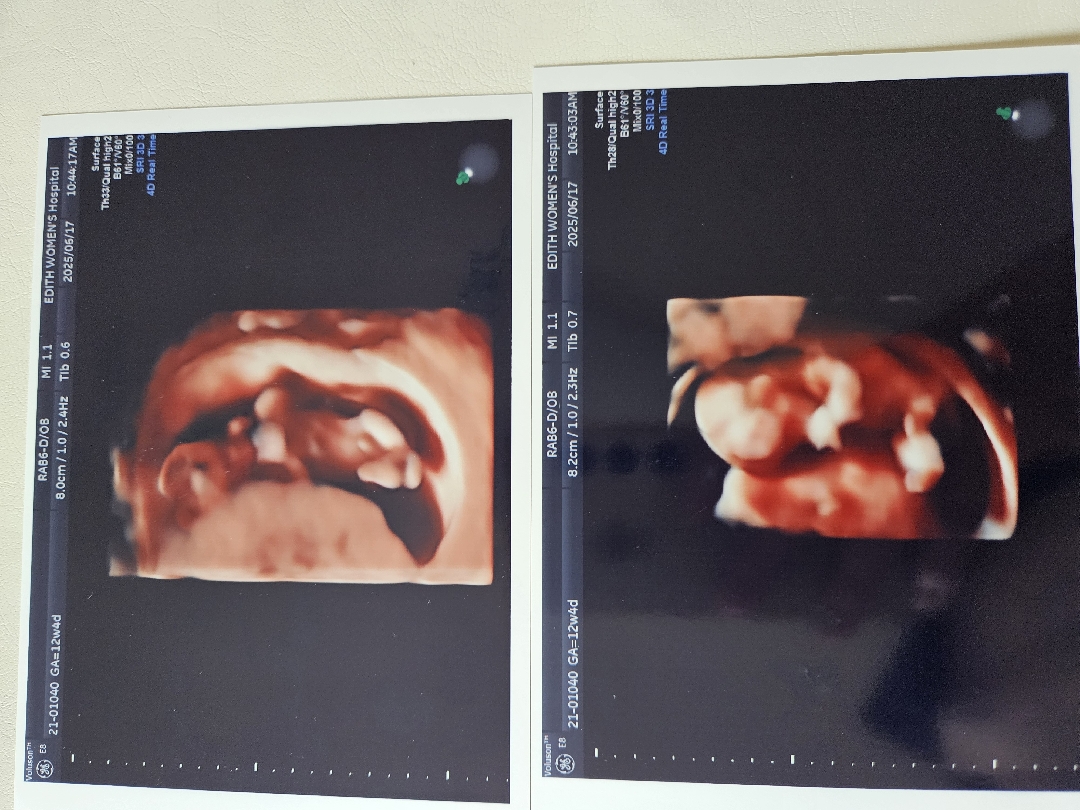

아들맞나요?

1차기형인검사하고 받은사진인데 아들같기도힌고 아닌거같기도하네요 뭘까용

제 11주6일차 정밀토음파랑 똑같은데 저 아들이에오

저는 12주때 여자랫는데 아직 15주 돼봐야 확정지을수 있을것 같아요 ㅎㅎ 근데 저는 1차 했을태 왜 저런 초음파사진 못 찍었지?? 이건 정밀초음파인가요??

저때는 여아나 남아 둘다나와있어서 시간지나봐야 알아용~